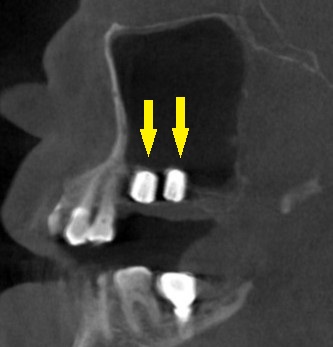

レントゲン、CTを撮影すると、骨幅は十分ですが、高さが3~4mmと、通常のインプラント埋入を行なうには、かなり不足でした。

何らかの骨造成が必要なのですが、年齢も考えて、あまり大変なことはしたくないとのご希望でしたので、人工骨を補填しての骨造成は行わず、ワイドショートインプラントで対応させていただくこととしました。

本日、左第一大臼歯に直径6.0mm長さ7mm、第二大臼歯部位に直径5.0mm長さ7mm、のインプラント埋入術を施行しました。

下の写真が手術前後のCTです。